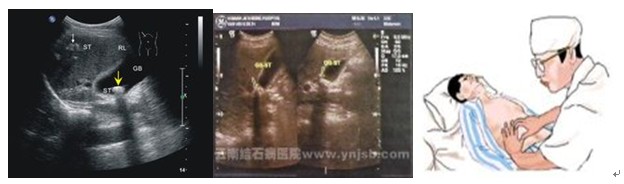

综上所述:HBv的现症感染,可根据下列任何一项指标阳性而确立:①血清HBsAg阳性;②血清HBVDNA或DNA多聚酶阳性;③血清IgM抗-HBc阳性;④肝内HBcAG和(或)HBsAg阳性,或HBVDNA阳性。肝超声波检查和心电图有异常改变。

临床观察:询问病史、体格检查,具有消化道症状、黄疸、肝脾大及ALT升高等肝炎表现,结合必要的化验检查及影像学检测,全面综合分析。